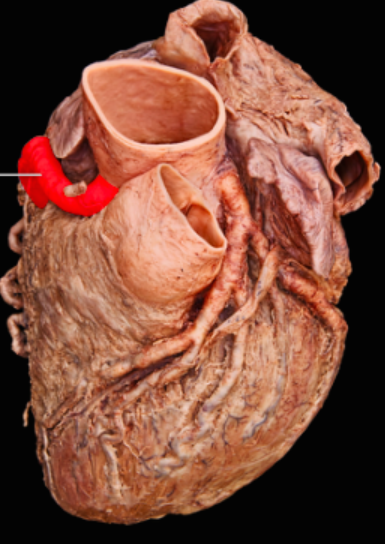

Name the valve and list the components of the valve

Aortic Semilunar Valve

nodule

lunulae

cusps